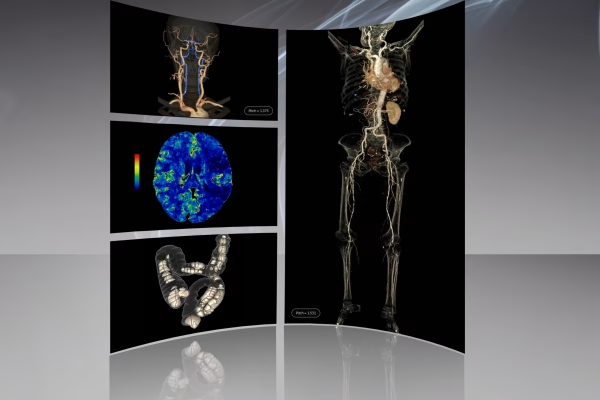

Scanner GE Optima CT520